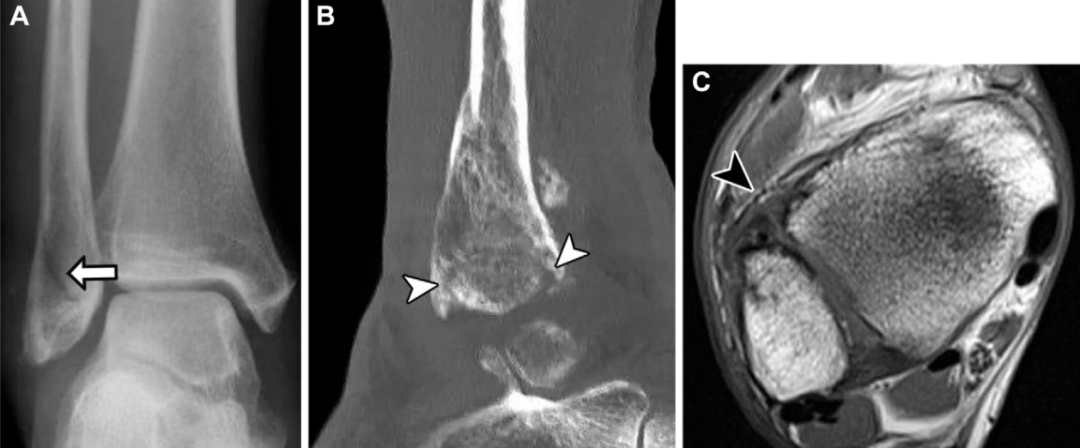

不稳定性损伤的MRI诊断要点

尽管MRI能精准评估韧带和骨性损伤,但无法对远端胫腓联合进行动态评估。因此,MRI可显示解剖学损伤,但不能直接确诊关节不稳,仅能通过间接影像学表现推断。MRI上提示胫腓联合不稳的关键征象包括:后下胫腓韧带完全撕裂、后踝骨折、三角韧带完全撕裂及胫腓联合近侧腓骨骨折。

下胫腓后韧带完全断裂是判断胫腓联合不稳的可靠指标,其敏感性为74%,特异性为 78%,阳性预测值为54%。后踝骨折对关节生物力学的影响与下胫腓后韧带完全断裂相当,且单独发生的概率极低,仅占所有踝关节骨折的1%~4%:

但该骨折常合并更复杂的损伤,包括双踝骨折、三踝骨折和腓骨近端骨折。约82%的Maisonneuve骨折患者会出现后踝骨折的症状和体征。尽管单纯三角韧带损伤通常为稳定性损伤,但当其与远端胫腓联合损伤并存时,会导致踝关节冠状面明显不稳。